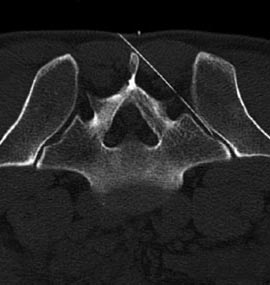

Zur Eingriffsplanung und Steuerung der Mikrotherapie werden die CT und die digitale Röntgendurchleuchtung verwendet. Durch diese Art der Planung und Kontrolle ist ein millimetergenaues Vorgehen möglich. Auf diese Weise wird die Verletzung wichtiger anatomischer Strukturen und Organe vermieden. Je nach Art des Eingriffs kann eine Kontrolle der Instrumente auch über ein Endoskop mit Glasfaserkabeln und Lichtleitern erfolgen.

Die korrekte Lage der Instrumente wird kontrolliert und ggf. korrigiert. Je nach Befund (bei der Halswirbelsäule relativ oft) muss die Instrumenten- oder Nadellage mittels der Gabe einer geringen Kontrastmittelmenge kontrolliert werden. An der Lendenwirbelsäule wird der Eingriff in Bauchlage durchgeführt, an der Halswirbelsäule in Rückenlage. Die Infiltration mittels Nadeln wird auch als diagnostisches Verfahren, als sogenannte Testinfiltration genutzt.

Abbildungen: rechts unten: Selektive Infiltration des Kreuzdarmbeingelenks (ISG), links oben: Mikrotherapie am Facettengelenk mit Kontrolle der Nadellage am Gelenkspalt, zweite Nadel im Wurzelkanal